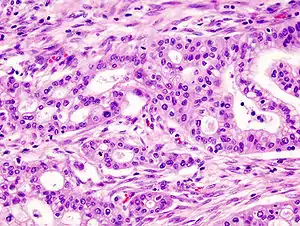

![]() Мікрофотознімок аденокарциноми підшлунковoї залози (фарбування гематоксиліном-еозином) Мікрофотознімок аденокарциноми підшлунковoї залози (фарбування гематоксиліном-еозином) | |